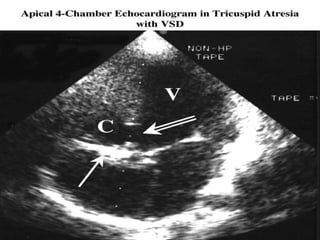

ECHOCARDIOGRAPHY.

Two-dimensional :

• Absence of the tricuspid orifice, marked hypoplasia of the

RV, and a large LV can be imaged in the apical four-chamber

view.

• 2. The bulging of the atrial septum toward the left and the

size of the interatrial communication are easily imaged in the

subcostal four-chamber view.

• In the most common muscular type, a dense band of echoes

is seen at the site, where tricuspid valve should be and the

anterior leaflet of the detectable atrioventricular valve is

attached to the left side of interatrial septum Apical and

subcostal four-chambered views are best to demonstrate The

anatomy

ECHOCARDIOGRAPHY. Two-dimensional : • Absenceof the tricuspid orifice, marked hypoplasia of the RV, and a large LV can be imaged in the apical four-chamber view. • 2. The bulging of the atrial septum toward the left and the size of the interatrial communication are easily imaged in the subcostal four-chamber view. • In the most common muscular type, a dense band of echoes is seen at the site, where tricuspid valve should be and the anterior leaflet of the detectable atrioventricular valve is attached to the left side of interatrial septum Apical and subcostal four-chambered views are best to demonstrate The anatomy • 3. The size of the VSD, the presence and severity of PS, and the presence of TGA should all be investigated. • 4. Patients with TGA should be examined for possible